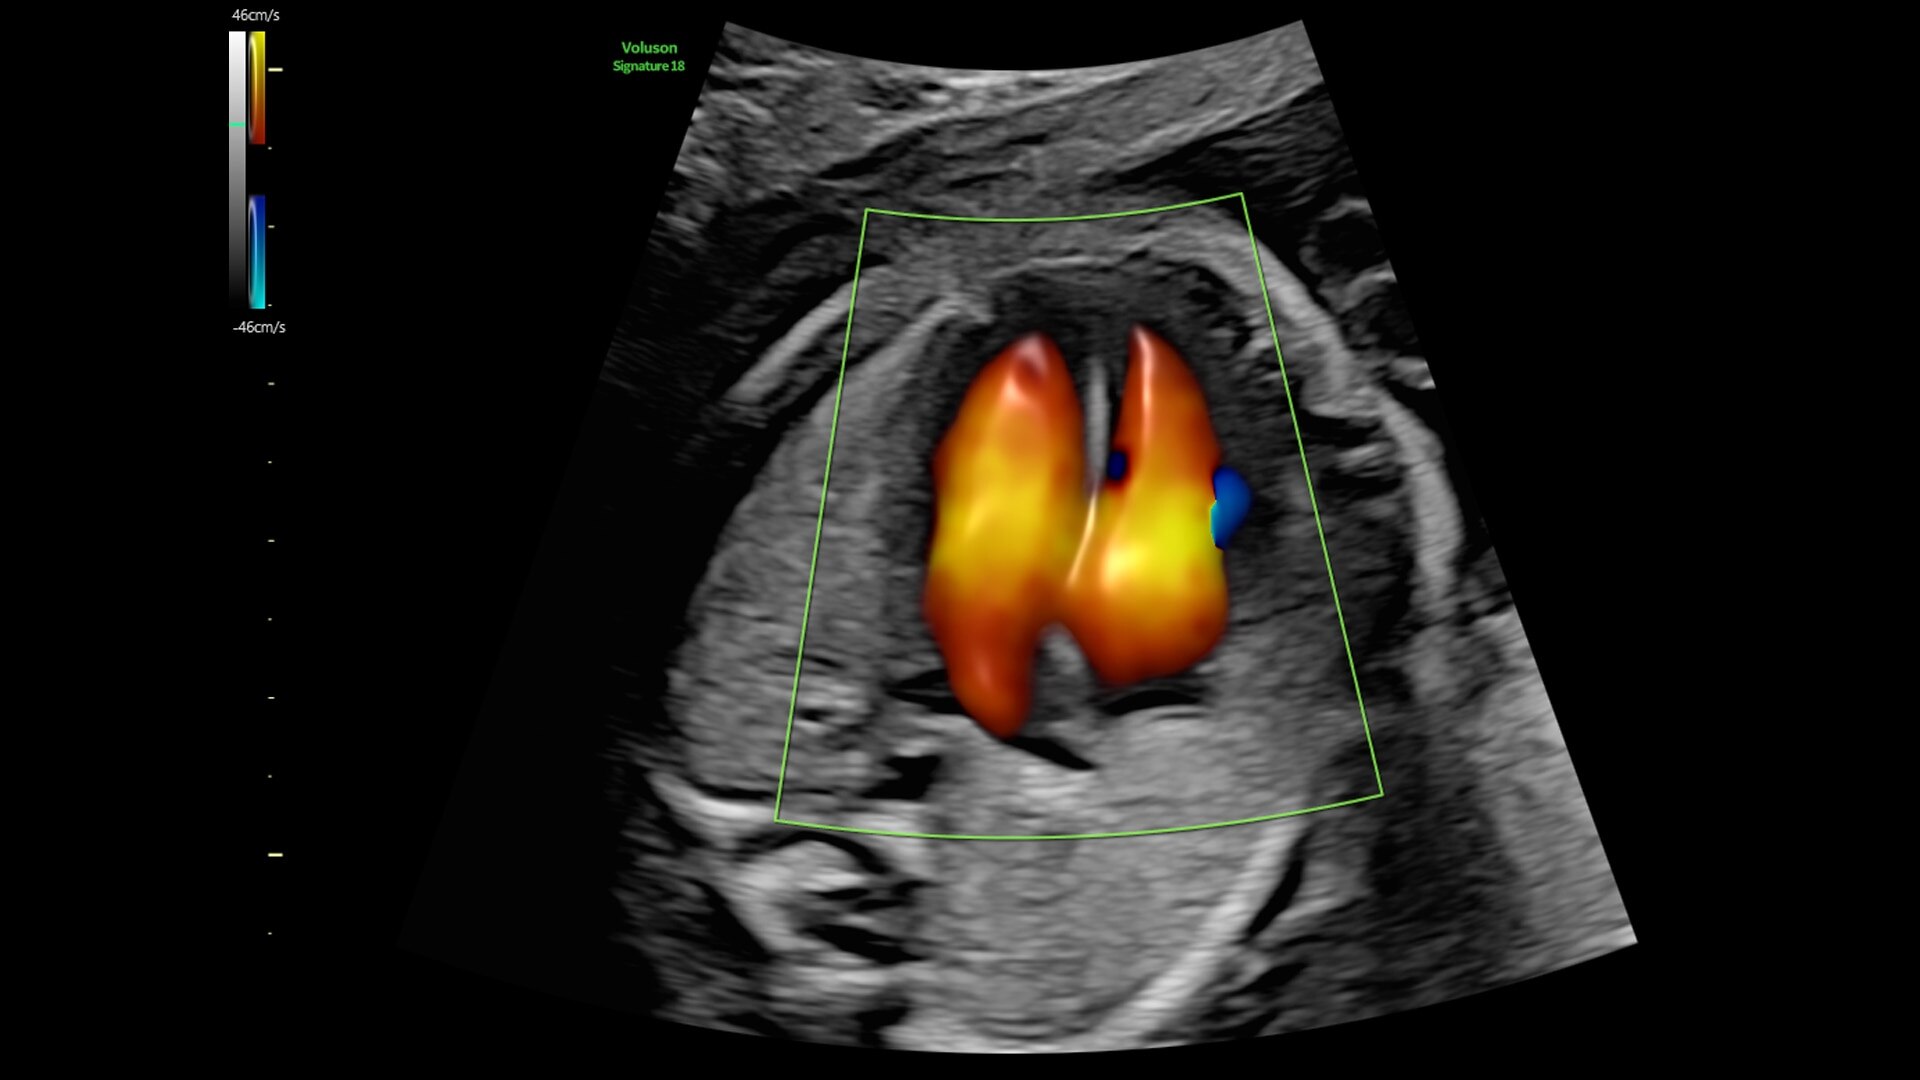

Fast, easy 3D-like blood flow visualization

Next level color Doppler delivers exceptional sensitivity for easy, fast visualization of blood flow, revealing even the tiniest vessels.

3-radiantflow-clinical-image-ci-en